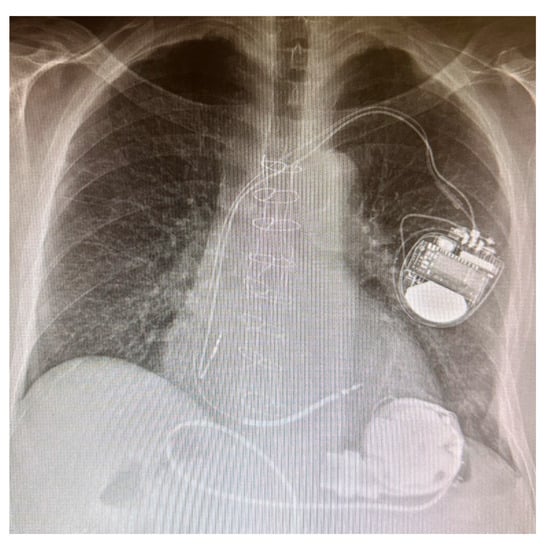

3. LVAD: A Machine to Supplement the Heart